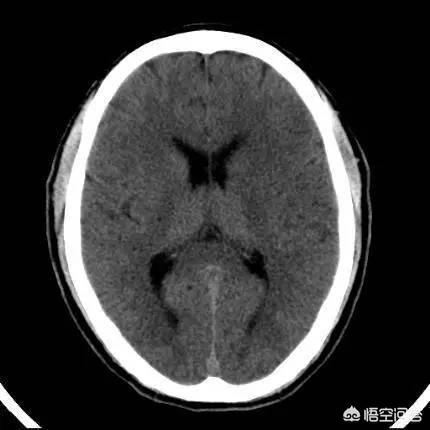

病院に送られた後、救急クリニックは徐さんのために緑色のチャンネルを開き、頭部のCT検査を完了し、出血病巣なし、血圧:170/92mmHg、心電図は「洞調律、aVF異常Q波、心筋梗塞の下壁を考える(時期は未定)」を示唆し、同時に血液ルーチン、トロポニン、凝固機能、心酵素をチェックした。異常は見つからなかった。その後、MRA検査で右側橈側冠動脈ラクナ梗塞が見つかり、NIHSSスコアは5であった。急性脳梗塞」として神経内科に緊急入院した。

何が起こったのか?その結果、ある日突然、体の半分が動かなくなり、脳梗塞のCTスキャンを受けるために病院に送られた。